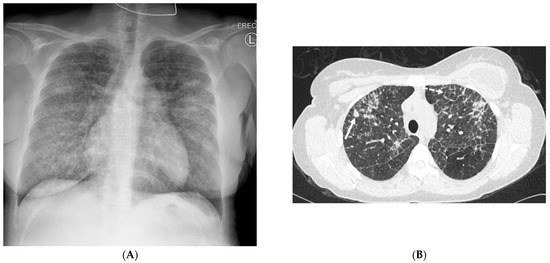

2.4. Pneumocystis Jiroveci Pneumonia (PJP)

6.2. Pulmonary Alveolar Proteinosis (PAP)